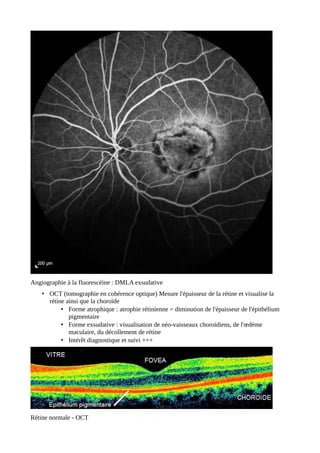

Angiographie à la fluorescéine

Non systématique

Visualise la perfusion rétinienne :

• Les néo-vaisseaux

• La perméabilité capillaire

• Les zones d'ischémie

OCT

Diagnostic et suivi de l'œdème maculaire